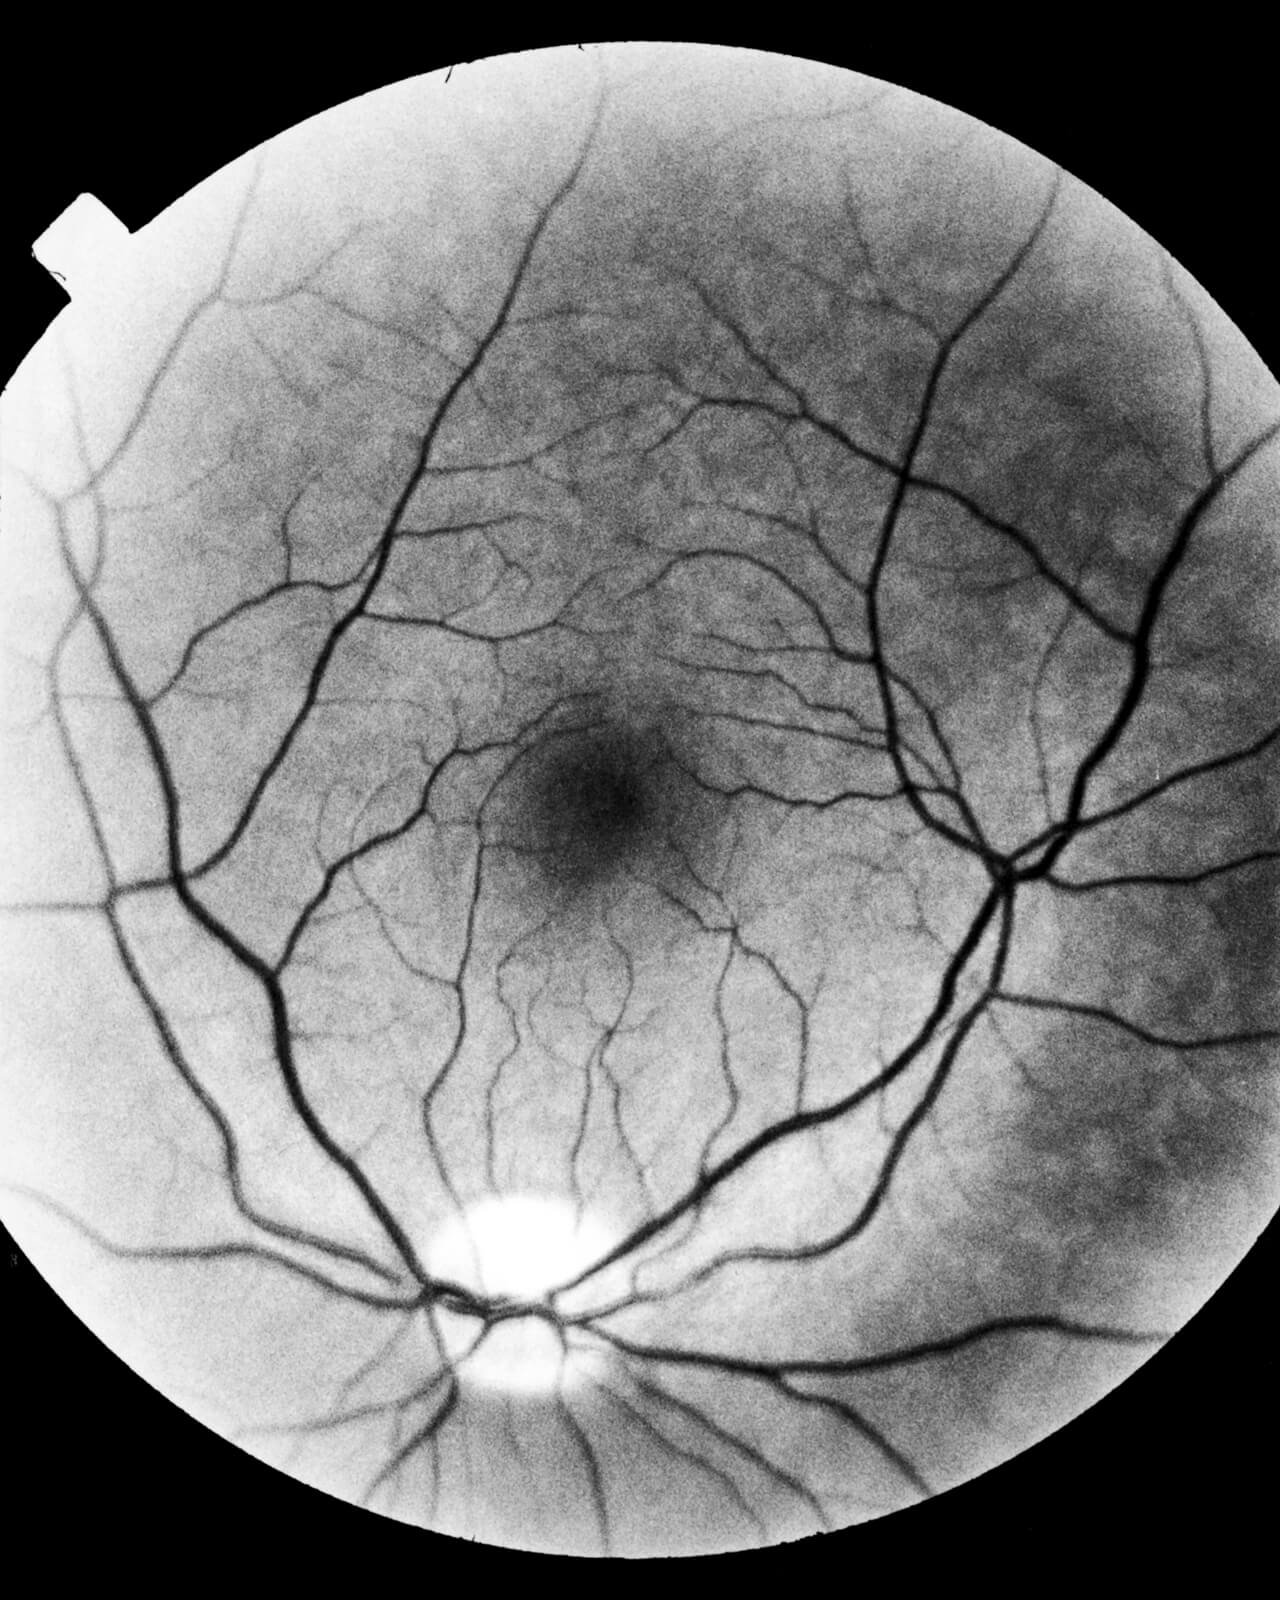

“It’s surprising how often memories appear to us in visual form, similar to snapshots in the psyche that only the time can erase. After all, sight is not only the product of the activity of our eyes, it is also and above all the gaze of our mind through memory. This visual nature of the past that gives shape to our memories does not fit in appearance with blindness; yet, I wanted to probe this aspect, trying to work visually on the fear of losing sight. Hence, starting from this contradiction, the search for a visual narration cannot fail to be closely linked to memory, although the sight ceases, what remains is the entirety of the experiences that time offers us to the extent that we exist and existence is nothing more than a continuous encounter between us, the world and what goes beyond us.” In June 2020 I found the angiographies of my grandfather from 1999, which certify the loss of sight in his right eye due to a thrombosis. Although not blind, the loss of stereoscopic vision changed many aspects of his life. I grew up flipping through his family albums and, as a photographer, the thought of losing sight initially shocked me. Nowadays sight is almost taken for granted. However, if we think that is possible to lose it, things change. This is why I decided to work on a universal fear, not just personal, that we can all have, trying to give value to images that, before being photographs, are memories.